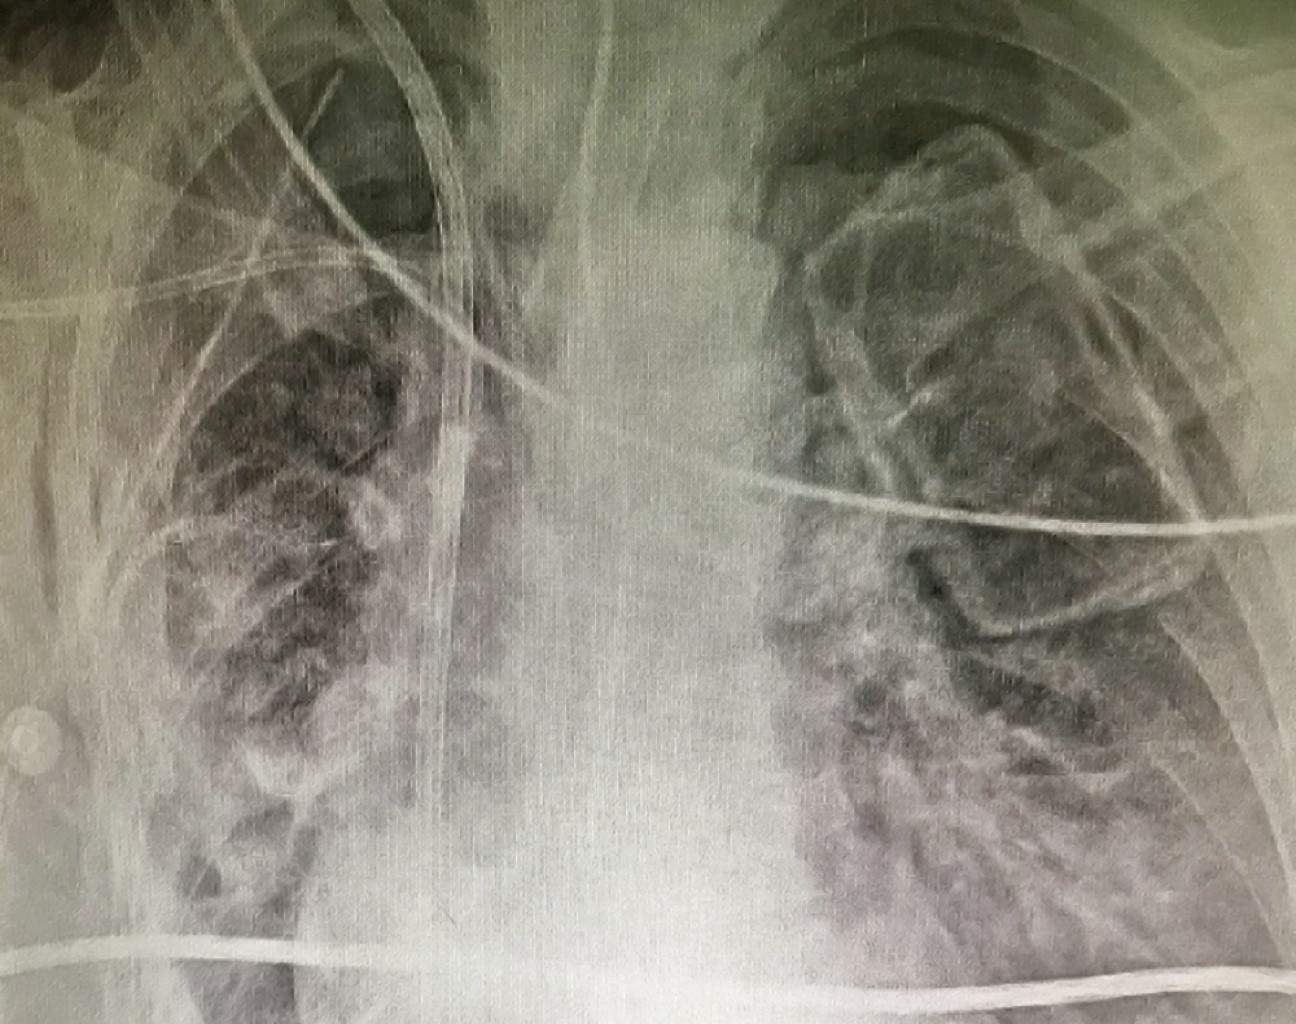

Se realiza primero videofibrobroncoscopia, sin evidenciar lesiones endobronquiales. Se continúa con toracotomía derecha amplia. Se logra resección completa del tumor, junto con fragmento de diafragma y parénquima pulmonar. Tumor de aproximadamente 1.5 kg, compatible con leiomiosarcoma de bajo grado, con márgenes de resección libres de lesión (Figura 4). La paciente logra buena expansión pulmonar en el posoperatorio inmediato. Se recupera en la Unidad de Cuidados Intensivos al inicio y después continúa en sala general, con buena evolución (Figura 5).

Figura 5